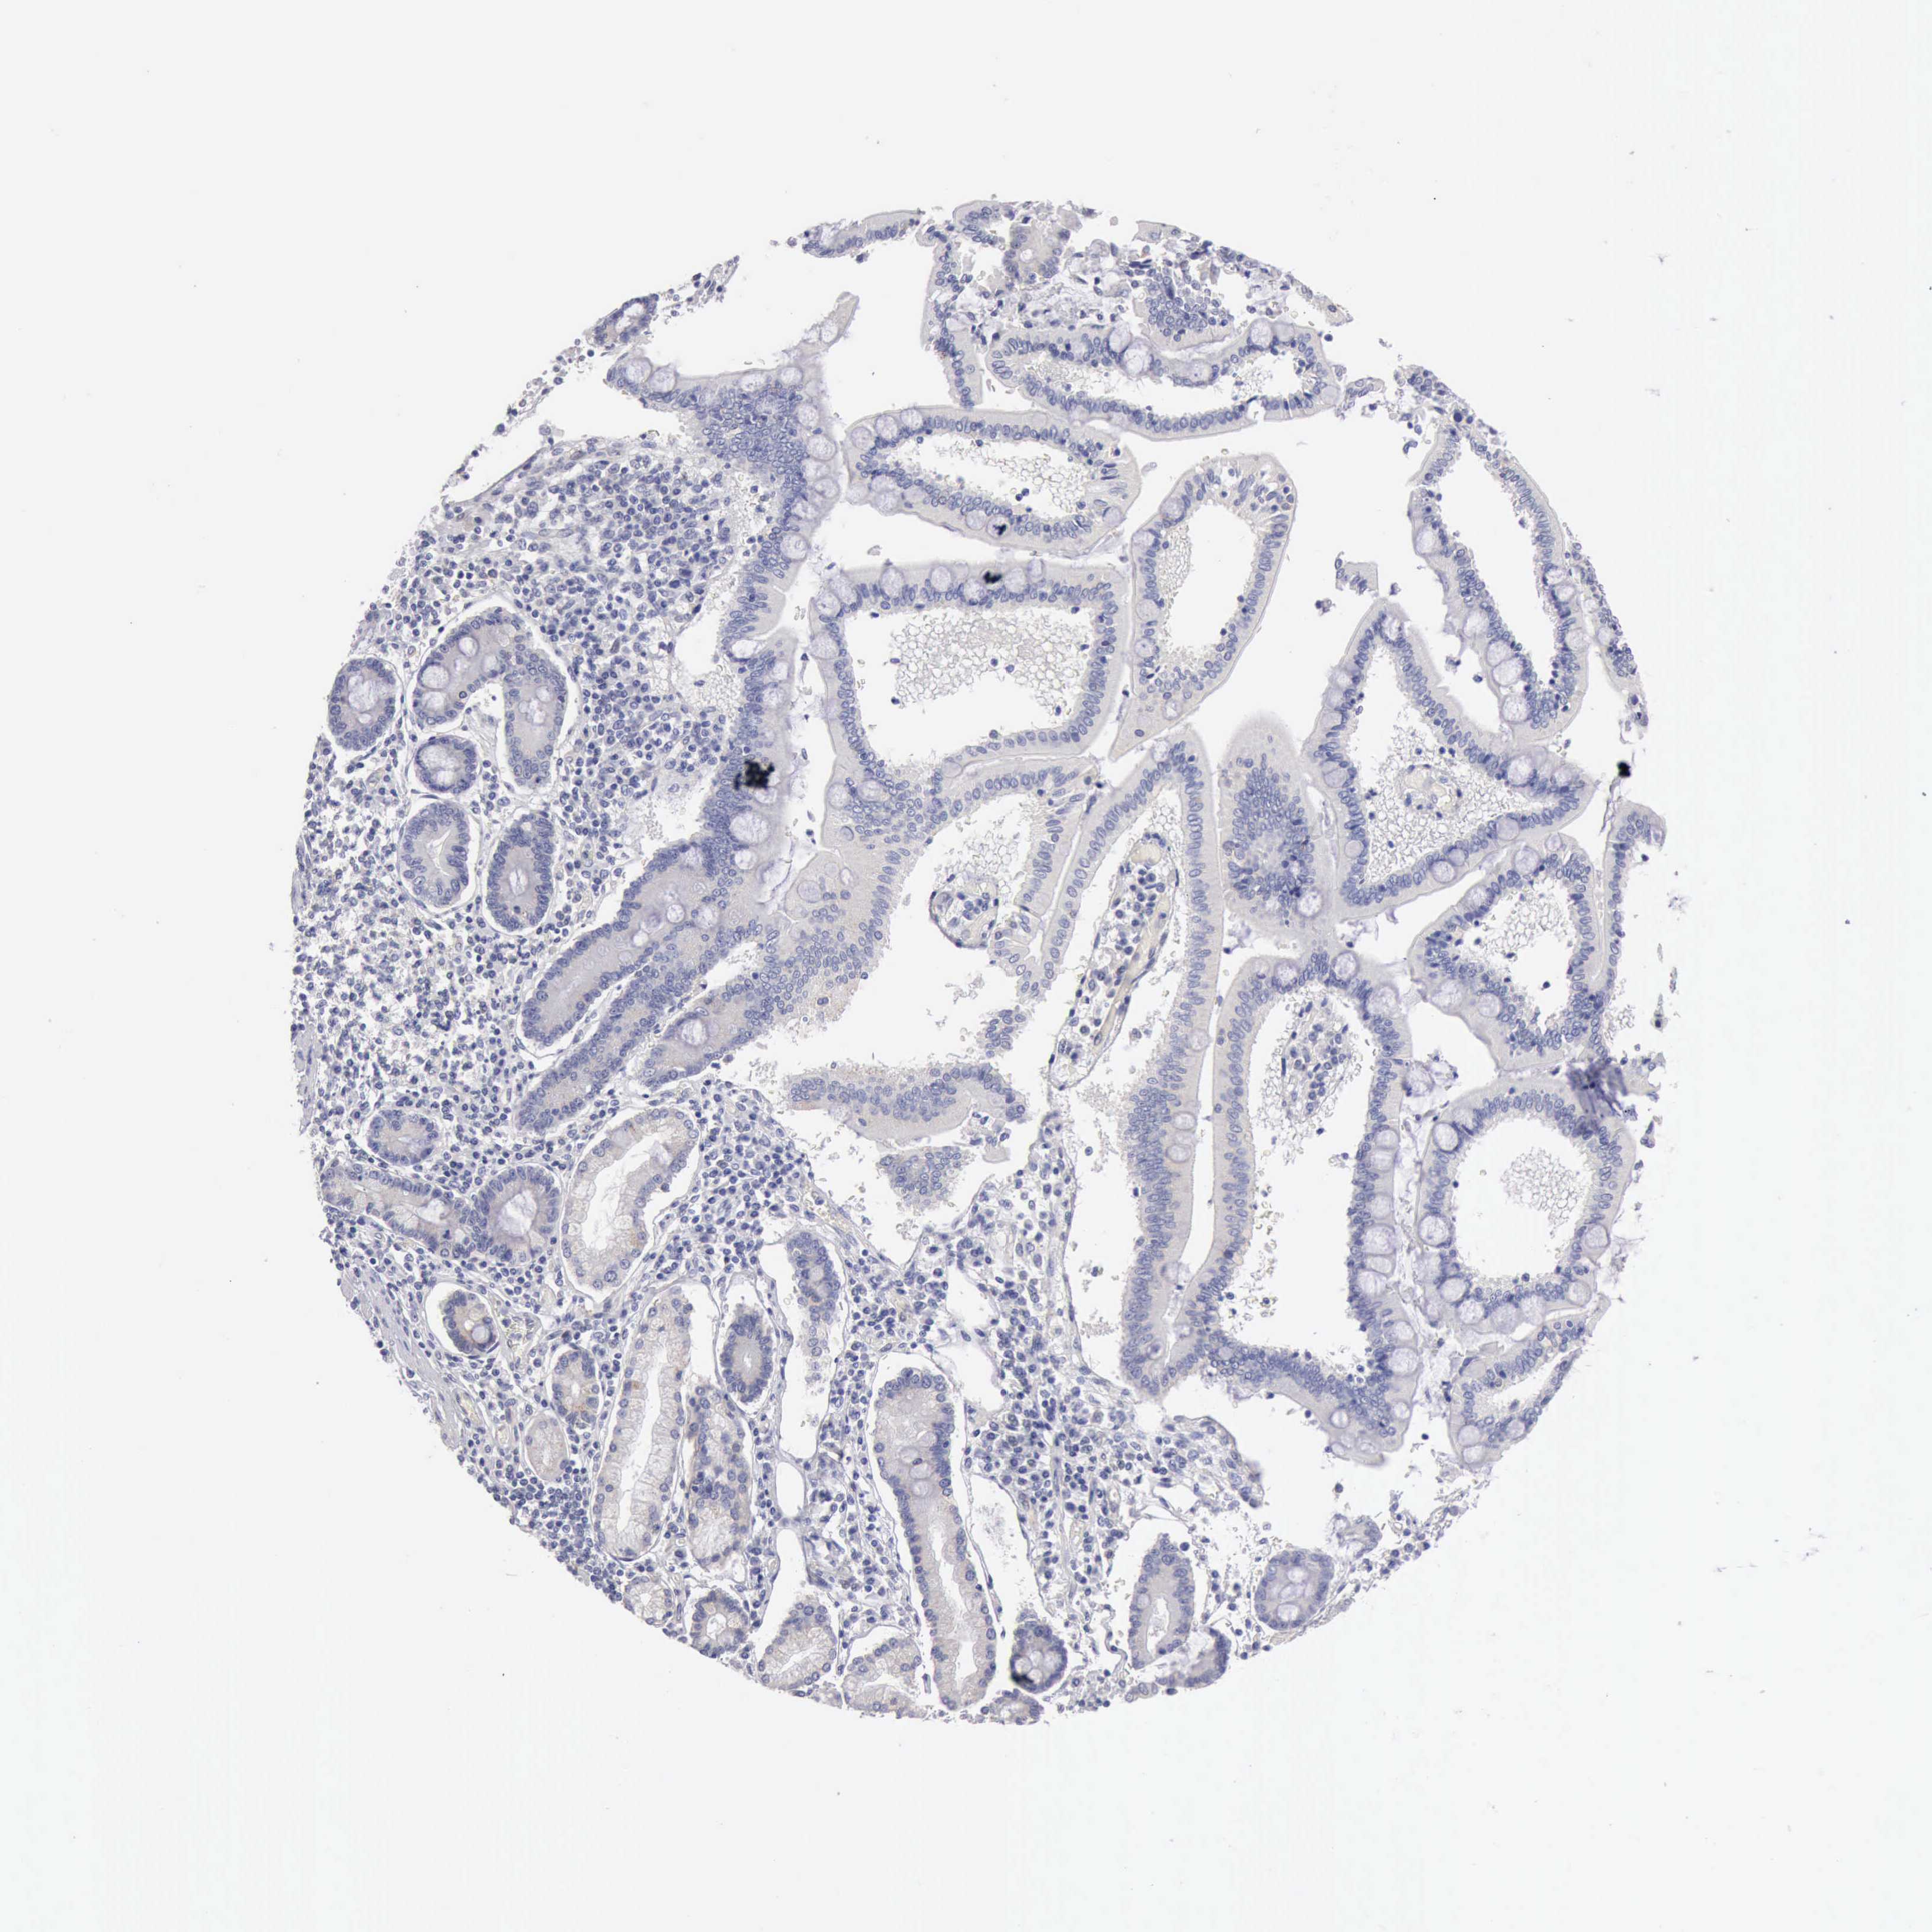

PANCREATIC CANCER - Protein expressioni

A mouse-over function shows sample information and annotation data. Click on an image to view it in a full screen mode. Samples can be filtered based on level of antibody staining by selecting one or several of the following categories: high, medium, low and not detected. The assay and annotation is described here.

Note that samples used for immunohistochemistry by the Human Protein Atlas do not correspond to samples in the TCGA dataset.

Antibody stainingi

Antibody staining in the annotated cell types in the current human tissue is reported as not detected, low, medium, or high, based on conventional immunohistochemistry profiling in selected tissues. This score is based on the combination of the staining intensity and fraction of stained cells.

Each image is clickable and will lead to virtual microscopy that enables deeper exploration of all samples and also displays staining intensity scores, fraction scores and subcellular localization as well as patient and tissue information for each sample.

Antibody HPA001462

Antibody CAB000157

Adenocarcinoma, NOS